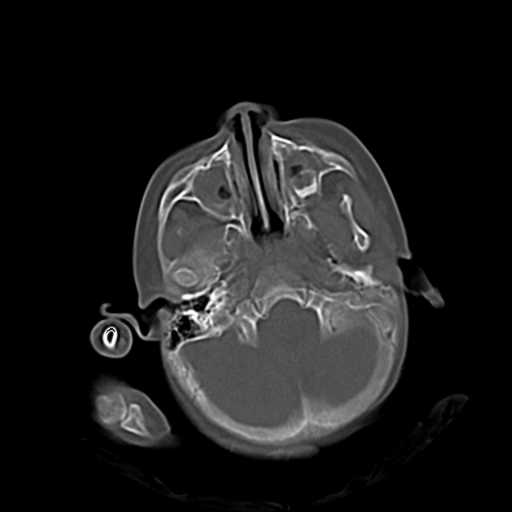

m,3y,外伤一天,无明显其它症状.

3.小脑以及右侧颞叶无明显异常,颅盖以及颅底诸骨未见明显骨折,双侧枕骨内板蛛网膜粒压迹多、略深。

1.右小脑半球外侧影为手指产生的伪影?硬膜外血肿?

右侧颅底后可疑颅窝骨折.

双侧双颌窦及筛窦内可见密度增高影,考虑付鼻窦炎,上颌窦后壁骨折.